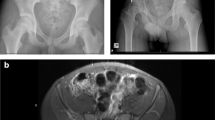

Adequate tumor resection margins are the most important goal for a successful tumor procedure in any patient. Resections should be based on a careful preoperative assessment of the response to preoperative (neoadjuvant) chemotherapy that is accomplished with careful review of preoperative MRI, CT, and positron emission tomography (PET) imaging that should assess the tumor size, soft tissue and osseous involvement, tumor inflammation, and proposed surgical margins [6]. The best assessment of the patient’s response to preoperative chemotherapy involves a comparison of both MRI and PET scan imaging before and after the first 10–12 weeks of preoperative chemotherapy [7, 8]. That comparison of imaging before and after preoperative chemotherapy is a critical sign of whether the patient’s tumor is responding to preoperative chemotherapy. The assessment of the neoadjuvant chemotherapy “response” with a comparison of MRI and PET imaging is an essential part of planning surgical margins in all patients treated with preoperative chemotherapy, because a good response to chemotherapy will allow closer surgical margins at resection and the possible preservation of important anatomic structures (Fig. 17.2). Close or smaller tumor margins (1.0–2.0 cm), however, are at higher risk for tumor contamination and subsequent tumor recurrence, whereas wider, greater margins (2.0 cm or greater), with the presence of a normal cuff of tissue, are theoretically at less risk of tumor recurrence [3, 9]. Evidence-based guidelines for determining the adequacy and quality of a tumor margin and the pathologic description of surgical margins are challenging and become more complex in the pelvis [10, 11].

The process of evaluating preoperative imaging should be determined with imaging guidelines. On T2 or STIR MR imaging sequences, the increased signal surrounding the tumor indicates inflammation and possible microscopic tumor at the tumor interface with surrounding normal tissues. With effective neoadjuvant preoperative therapy, this zone may disappear or shrink and allow a closer margin of resection [12] (Fig. 17.2). PET scan imaging is a quantitative assessment of the glucose uptake by the tumor as reflected in the standard uptake value (SUV). A 50% reduction in the PET SUV will typically reflect a good response when comparing pre- and post-systemic therapy PET scans.

Type II pelvic Resection and reconstruction—preoperative imaging (a–c), PET scan (d), navigation margin (e), postoperative composite allograft/THR (f). (a) Preoperative pelvic X-ray. (b) Preoperative pelvic MRI (coronal T2). (c) Preoperative pelvic MRI (axial T2). (d) PET scan image of tumor. (e) 3D image of navigated pelvic procedure. (f) Postoperative Type II alloprosthetic reconstruction